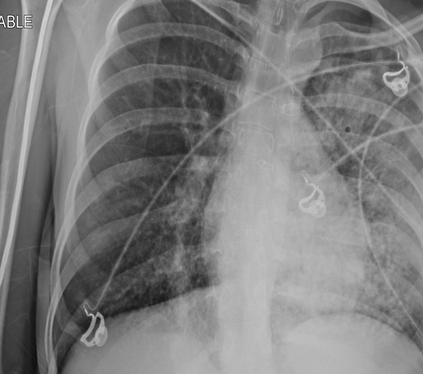

Tuberculosis remains a critical global health issue, particularly in resource-limited and remote areas. Early detection is vital for treatment, yet the lack of skilled radiologists underscores the need for artificial intelligence (AI)-driven screening tools. Developing reliable AI models is challenging due to the necessity for large, high-quality datasets, which are costly to obtain. To tackle this, we propose a teacher--student framework which enhances both disease and symptom detection on chest X-rays by integrating two supervised heads and a self-supervised head. Our model achieves an accuracy of 98.85% for distinguishing between COVID-19, tuberculosis, and normal cases, and a macro-F1 score of 90.09% for multilabel symptom detection, significantly outperforming baselines. The explainability assessments also show the model bases its predictions on relevant anatomical features, demonstrating promise for deployment in clinical screening and triage settings.